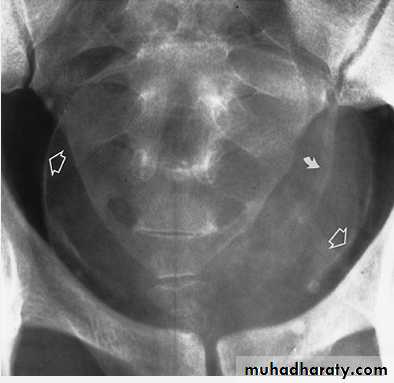

Infestation With Schistosoma haematobium. Plain radiograph demonstrates calcification in the wall of the bladder (open arrows) and in the wall of the left ureter (curved arrow). The bladder is filled with urine